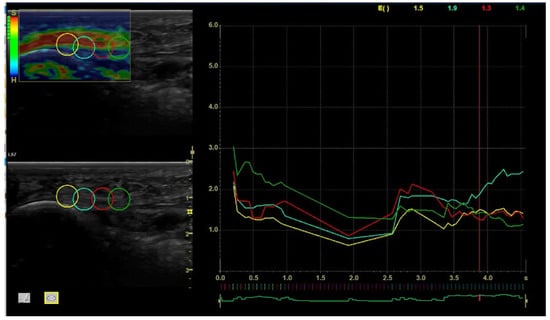

The stiffness color scheme was red (hard), green (medium), and blue (soft). The color histogram was analyzed, and subsequently, the mean intensity of each color component of the pixels within a standardized area was computed. As indicated by the manufacturer guidelines, the exact raw strain value was calculated from a 5 mm circle in a supple region of the selected area [11,21,22]. Following the manufacturer’s recommendations, the approved compression size was assessed by means of a quality control incorporated into the software. It consists of green bars displayed on a screen, with five bars being the most suitable and one the least suitable. The measured images were of the highest quality, as only sequences with green bars were included.

The SEL values obtained ranged from 0 to 6, where 0 means the softest and 6 the hardest tissue. In addition, there is a representative bar scale with the hardest tissue being shown in red and the softest tissue shown in blue, as well as by the letter “S” (soft) on the bar scale’s top and by the letter “H” (hard) on the bar scale’s bottom. (Figure 1).

This study aimed to show the changes that occur in the viscoelastic properties of the PF measured by SEL after the six applications of a 448 kHz CRMR in active healthy participants and how these changes last over time, specifically tested through one- and three-month follow-ups. Patients received six interventions in the plantar fascia of the dominant lower limb for 3 weeks using 448 kHz CRMR. The results from the present study show that the effects of CRMR on the plantar fascia elasticity may last up to one month in a healthy population after a 3-week treatment program when compared to the controls, specifically following the medial process of calcaneal tuberosity (See Figure 1, points 1 and 2). However, there were no elastic changes when analyzing points 3 and 4.

Figure 1. Region of interest (ROI) and SEL measurements. Note: left to right: point 1: PF insertion to the calcaneus; point 2: body of the plantar fascia in the mid-proximal portion; point 3: body of the plantar fascia in the middle portion; point 4: body of the plantar fascia in the mid-distal portion.